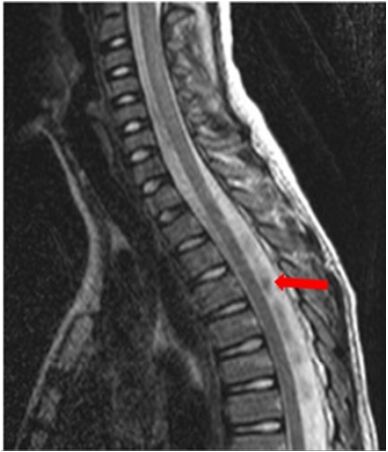

59.9 歲男性。下圖為其 T2 加權影像。箭頭所指其最適當的診斷為何?

(A)腦脊髓液流動假影(CSF flow artifact) (B)脊髓動靜脈畸形(spinal arteriovenous malformation) (C)脊髓內出血(spinal intramedullary hemorrhage) (D)化膿性膿腫(pyogenic abscess)